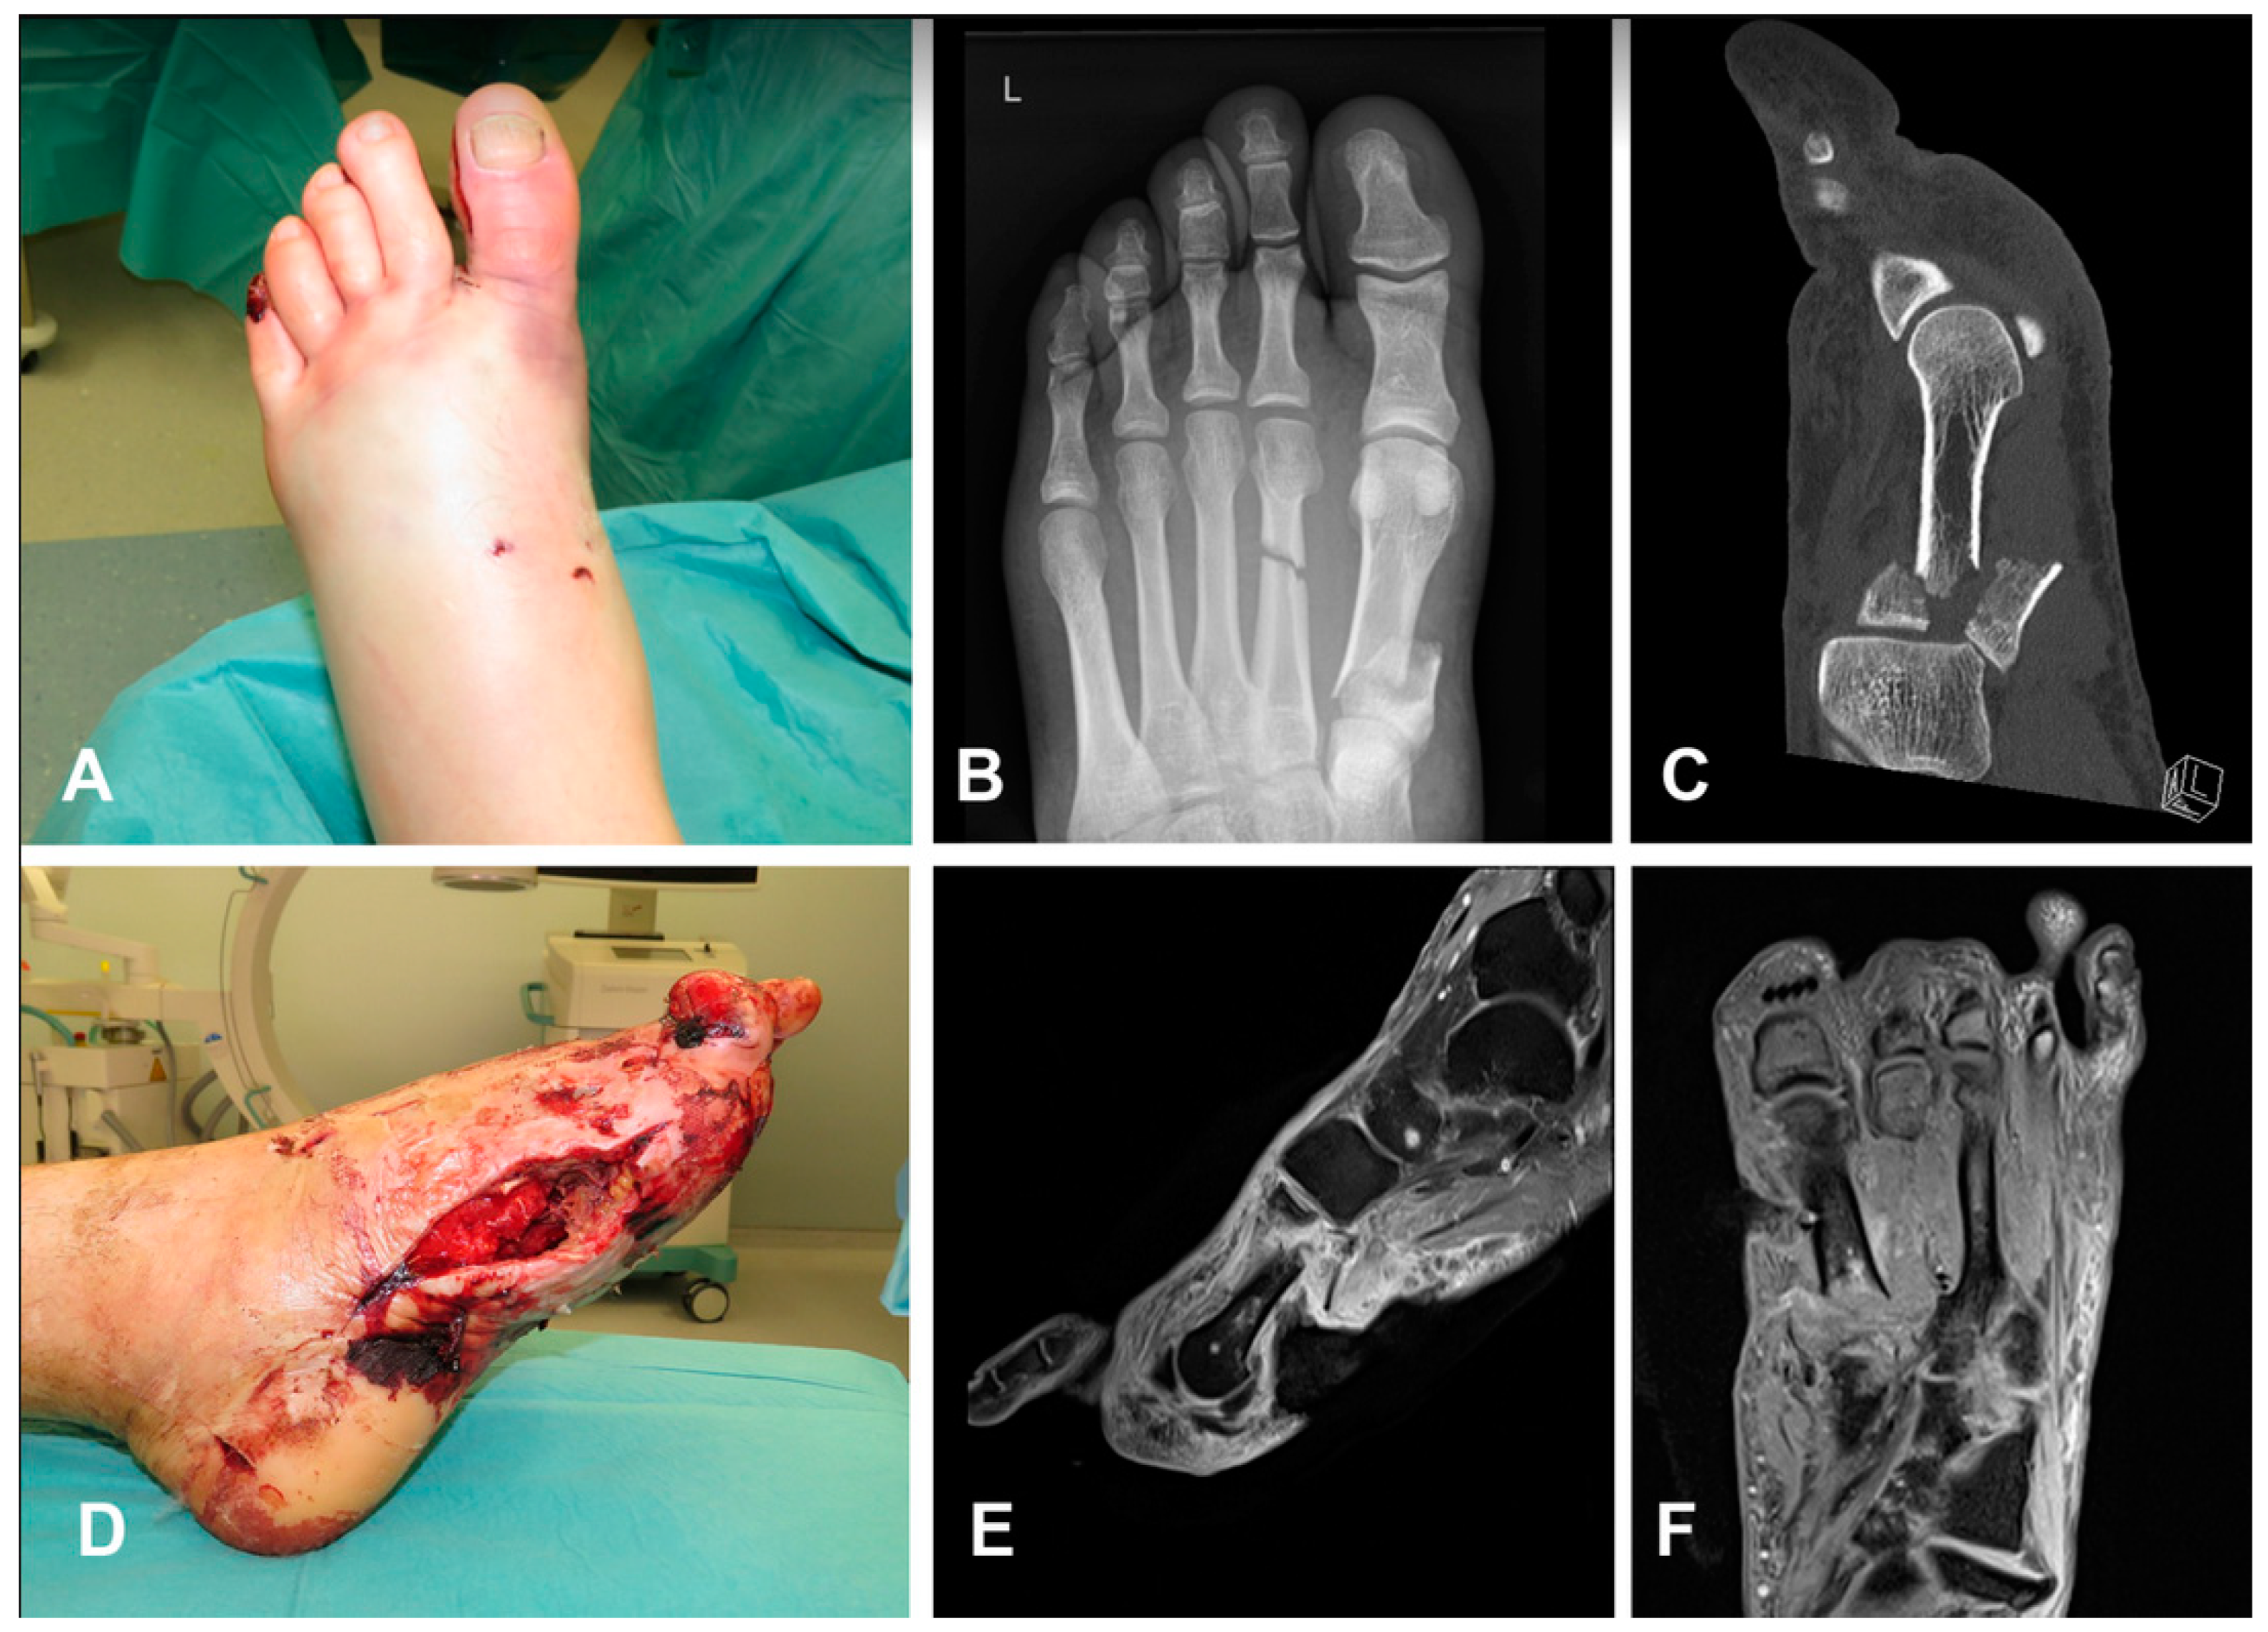

A 33-year-old smoker male presented a closed fracture of the I and II metatarsus after a motorcycle accident. The patient underwent emergency dorsal and medial fasciotomies, associated with external fixation. Fasciotomies were treated via negative pressure therapies. Due to jeopardized vascularization after trauma, the orthopaedic team subsequently amputated the thumb, while bone fragments incurred in progressive necrosis, with loss of the first metacarpal base (Figure 2). A double-flap treatment was then planned: this treatment was a cortico-periosteal FMC associated to a coverage ALT flap. The ALT flap was anastomosed to the tibialis posterior vessels, while the FMC was anastomosed sequentially to the ALT pedicle (descending branch). The post-operative course was uneventful with no recurrence of the infection. A post-operative X-ray showed a good integration of the bone vascularized graft at 16 weeks. A skin flap liposuction was performed 12 months post-operation. Walking activities could be resumed after 12 weeks, with progressive charge and physiotherapy until complete recovery (Figure 3).

Figure 2. A 33-year-old smoker male presented a closed fracture of I and II metatarsus after a motorcycle accident (AC). Patient underwent emergency dorsal and medial fasciotomies, associated with external fixation. Fasciotomies were treated by negative pressure therapies (D). Due to jeopardized vascularization after trauma, orthopaedic team subsequently amputated thumb, while bone fragments incurred in progressive necrosis, with loss of first metacarpal base (E,F).